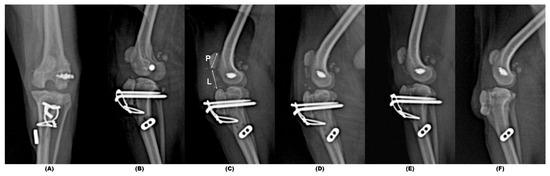

2. Case Description

3. Results